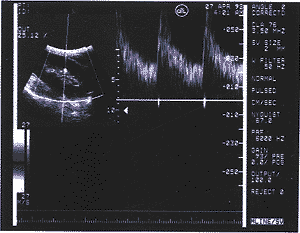

4、观察组间彩超所示血流信号的差异:ATN患者肾实质血流信号极稀少,肾髓质内 可显示多条动静脉短路的花色血流信号(图1),急性排异者肾叶间动脉和弓形动脉的彩色血 流信号不连续,脉冲性彩色血流信号间存在血流信号的中断,部分患者尚可示舒张期花色血 流(返流)(图2);梗阻者叶间动脉和弓形动脉呈“脉冲性静脉血流”信号,收缩期与舒张期 血流信号的色彩变化较少(图3)。

图1 ATN引起的DGF 肾实质内血流信号稀少,肾髓质内可见动静脉短路,导致肾叶间动脉阻力下降

图2 急性排异者引起的DGF 肾内动脉血流

信号不连续叶间动脉血流阻力大